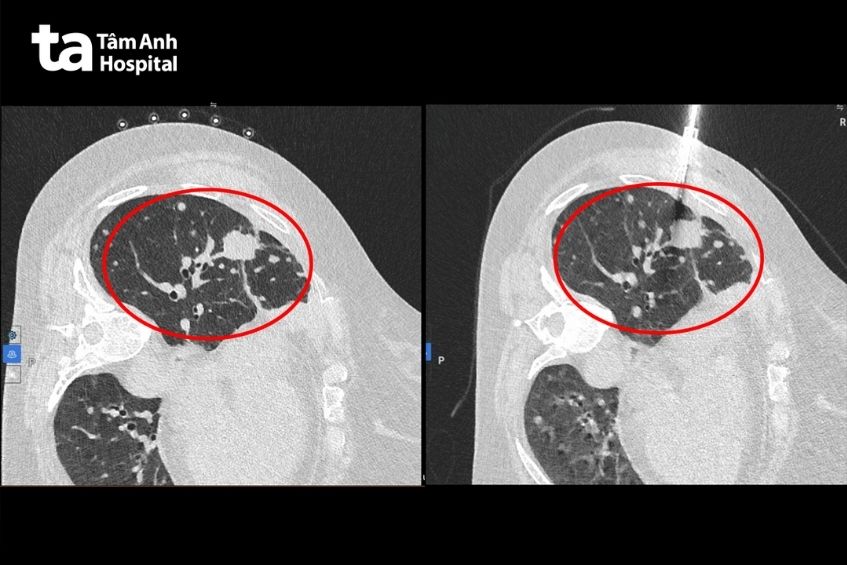

Tháng 10/2025, bà Hòa bị đau ngực nhiều hơn, chụp CT thấy tổn thương tăng kích thước lên 4 cm. Các bác sĩ đã tư vấn hướng sinh thiết u phổi để tìm đột biến gen kháng thuốc. Bệnh nhân hiểu rõ lợi ích của việc này nên một lần nữa quyết tâm tiếp tục theo đúng lộ trình điều trị.

Ê kíp bác sĩ chỉ định chụp CT scan xác định chính xác vị trí, độ sâu và đường đi an toàn nhất để đưa kim vào khối u, tránh các mạch máu lớn, xương và các cơ quan khác. Sau đó, đánh dấu trên da, đưa kim vào u dưới hướng dẫn của hình ảnh CT để lấy mẫu mô, đảm bảo an toàn, giảm nguy cơ tràn khí màn phổi hoặc ho ra máu sau sinh thiết.